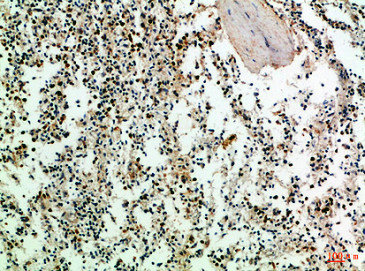

圖片:

應用范圍:IHC,ELISA

Application Recommended Dilution IHC IHC-p:1:50-300 ELISA 1:10000-20000 -

- the immunohistochemical staining patterns of CD3 and CD20 in Malignant Lymphoma Cells, were investigated. PMID: 28442514